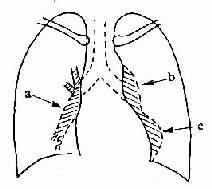

除肺、胸基礎疾病及急性肺部感染的特徵外,尚可有肺動脈高壓征,如右下肺動脈乾擴張,其橫徑≥15mm;其橫徑與氣管橫徑之比值≥1.07;肺動脈段明顯突出或其高度≥3mm;右心室增大征(圖2-3-3),皆為診斷肺心病的主要依據。個別病人心力衰竭控制後可見心臟外影有所縮小。